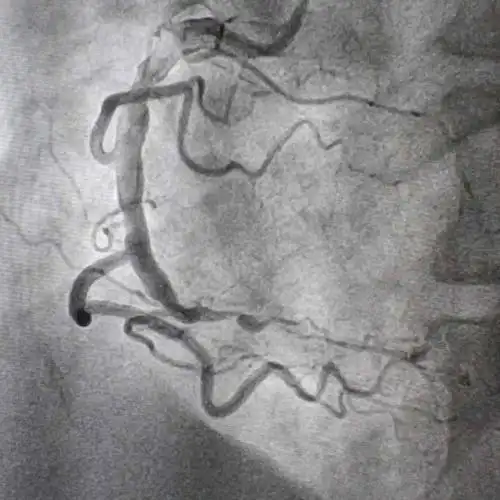

造影狭窄图

右冠脉两处重度狭窄,近端那个狭窄太严重了,说堵死就堵死了,一旦堵上

冠状动脉狭窄的血管造影

支架置入术前:右冠状动脉远端闭塞病变

冠脉造影图片